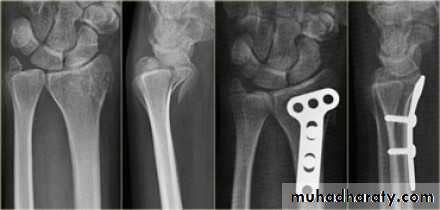

Upper limb

Fall on out stretched hand

xray